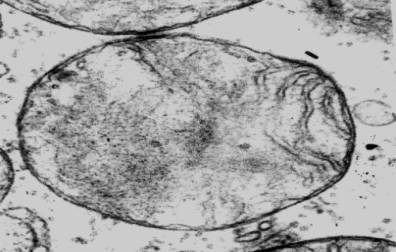

Следует

заметить, что в участках предсердий, отдаленных от зон ишемии, на

светооптическом уровне наблюдалась сохранная тканевая структура сократительного

миокарда. Апоптотические явления не были характерны для этих участков, однако,

с помощью электронной микроскопии мы наблюдали ряд ультраструктурных изменений

в составе митохондриального аппарата на 7-е и 14-е сутки подострого действия

сиднокарба (рис. 3,4).

Рис. 4. Кристолизис

в составе межмиофибриллярных митохондрий в

саркоплазме кардиомиоцита левого ушка сердца крысы на

14-е сутки

формирования экспериментального психоза. Ув.:

×25000.